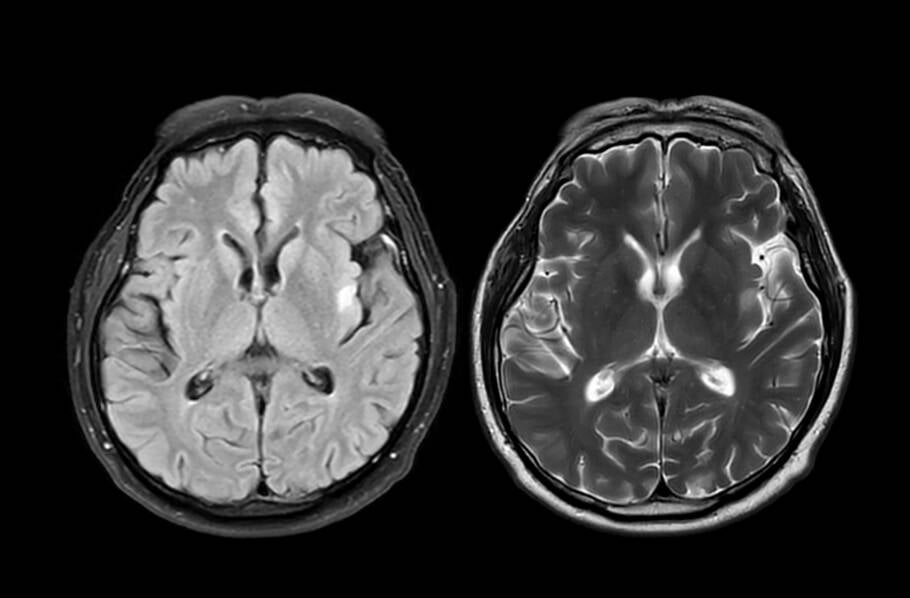

Com base em dados genéticos de cérebros humanos e registros médicos, os pesquisadores identificaram que o Alzheimer afeta diferentes células cerebrais de formas específicas. Os neurônios apresentavam alterações genéticas ligadas à comunicação entre células, enquanto as células gliais mostravam falhas em processos de suporte e limpeza do cérebro.

Além disso, exames pós-tratamento revelaram menos inflamações, menos acúmulo de proteínas tóxicas e até aumento no volume do hipocampo, área crítica para a memória.

Análises genéticas mostraram que a combinação dos remédios reprogramou as células cerebrais doentes para um estado mais próximo do saudável. Nos neurônios, genes responsáveis pela formação e manutenção das sinapses foram reativados. Já nas células gliais, genes relacionados à sustentação neuronal, à remoção de resíduos e à estabilidade estrutural do cérebro também foram restaurados.